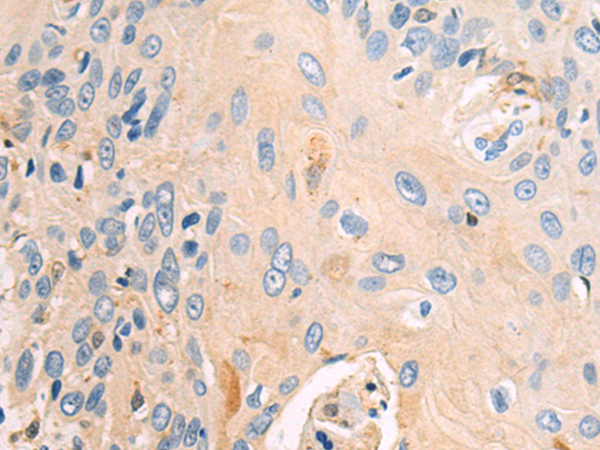

分类: 科研抗体货号: P06879别名: CTLO; HAMSV; HRAS1; RASH1; p21ras; C-H-RAS; H-RASIDX; C-BAS/HAS; C-HA-RAS1应用: WB,IHC反应种属: Human, Mouse, Rat